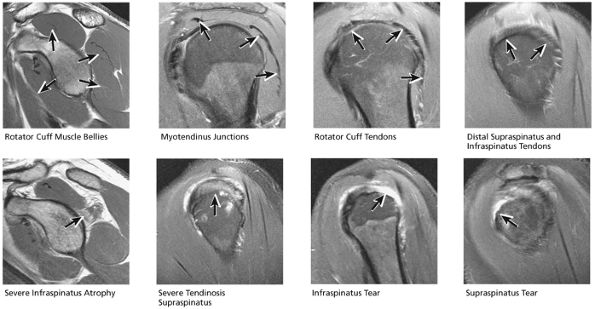

FIGURE 8.32 Rotator Cuff.